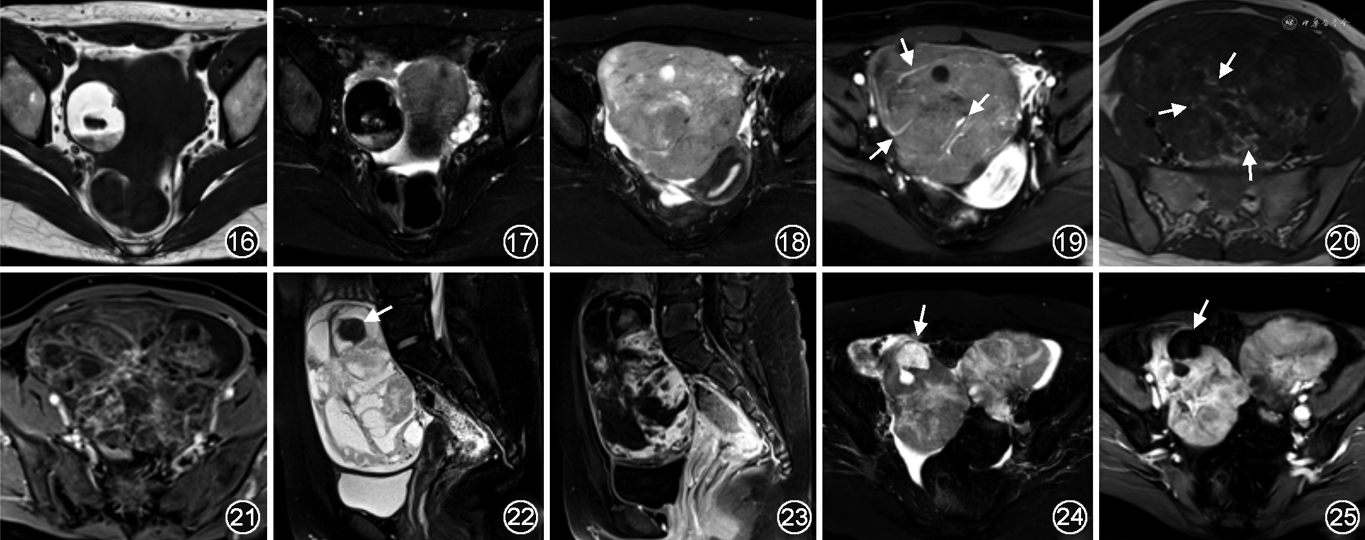

1.良性生殖细胞肿瘤:最常见者为成熟囊性畸胎瘤(mature cystic teratoma,MCT),占95%[14],由内、中、外胚层组织中2~3个组成,也可向单胚层分化,如卵巢甲状腺肿。MCT单侧多见,5%~10%为双侧。典型MRI表现为囊性肿块伴瘤内脂肪,脂肪成分在T1WI和T2WI均呈高信号,脂肪抑制序列信号明显降低(图16,17)。头结节(Rokitansky结节)表现为从内壁突向腔内的类圆形或不规则形隆起,可含多种组织成分,故信号混杂,增强呈轻度环状强化。MCT可呈纯囊性,仅少量脂肪位于囊肿边缘或分隔,易误诊为囊腺瘤;约6%不含脂肪,囊液T1WI呈中等高信号,脂肪抑制无明显降低,易误诊为内膜样囊肿[4]。卵巢甲状腺肿典型MRI表现为囊性为主或囊实性肿块,实性区内或邻近见点状T1WI高信号,囊性区T2WI见“真空征”,实性区明显强化。

(1)无性细胞瘤,最常见,约5%的肿瘤可分泌β-绒毛膜促性腺激素,血清乳酸脱氢酶和碱性磷酸酶常非特异性升高。典型MRI表现为分叶状、信号较均匀的实性肿块(图18,19),出血和坏死少见,DWI明显扩散受限,增强后中度强化。瘤内纤维血管分隔为特征征象,T2WI呈低或高信号,增强后轻度或明显强化,取决于纤维和血管的比例以及是否合并水肿[4,14]。

(2)未成熟性畸胎瘤,是第二常见的恶性生殖细胞肿瘤,肿瘤含2~3个胚层,由分化程度不同的未成熟胚胎组织构成。典型表现为信号混杂的囊实性或实性肿块,由脂肪、钙化、液体及软组织等多种组织成分混合而成,DWI呈不同程度扩散受限,增强后实性成分呈不同程度强化(图20,21)。对侧卵巢可伴MCT。肿块较大时易发生盆腹腔转移,常见于大网膜、后陷凹、膈下和肝脏表面[4]。

(3)卵黄囊瘤,是第三常见的恶性生殖细胞肿瘤,患者血清甲胎蛋白和β-绒毛膜促性腺激素可不同程度升高。单侧卵巢多见,双侧约占5%,肿瘤生长迅速,常发生明显出血和坏死液化,呈巨大囊实性肿块,T1WI和T2WI呈低、等、高混杂信号;实性成分形态极不规则,DWI扩散受限,呈明显不均匀性强化,亮点征是特征性征象,源于扩张的肿瘤血管(图22,23)。肿瘤可破裂,表现为囊壁连续性中断,盆腹腔大量积液[4]。

转移瘤占所有卵巢肿瘤的5%~7%,占卵巢恶性肿瘤的10%~30%。原发部位多为胃和结直肠,其次是乳腺、阑尾和子宫,源自胰腺、胆道和肺的转移瘤少见。卵巢转移瘤多发生于绝经期前女性,平均年龄为44岁。(1)胃癌卵巢转移常为双侧、不对称、边缘较清晰的实性或囊实性肿块,实性区常见多发类圆形囊变(图24,25)。肿块T1WI呈等、低信号,T2WI信号及增强表现多样,间质胶原反应明显时呈相对低信号及明显持续性强化;黏液含量明显时呈明显高信号及轻度强化或无强化,具有一定特征。(2)源自结直肠和阑尾的卵巢转移瘤常为双侧,以多房囊性为主,少数为囊实性肿块。信号特点与原发黏液性肿瘤类似,但原发黏液性肿瘤体积更大,极少双侧发生。(3)其他来源转移瘤。来源于乳腺癌的卵巢转移瘤多较小,多为双侧实性肿块。子宫肿瘤中子宫内膜癌的卵巢转移瘤更常见,呈囊实性或囊性为主[4]。临床工作中需注意,因囊性肿块较大较软,双侧病灶紧贴时易误认为单侧卵巢来源,需多方位仔细观察分析,避免误诊。另需注意有时患者无原发肿瘤病史,以盆腔肿块就诊。